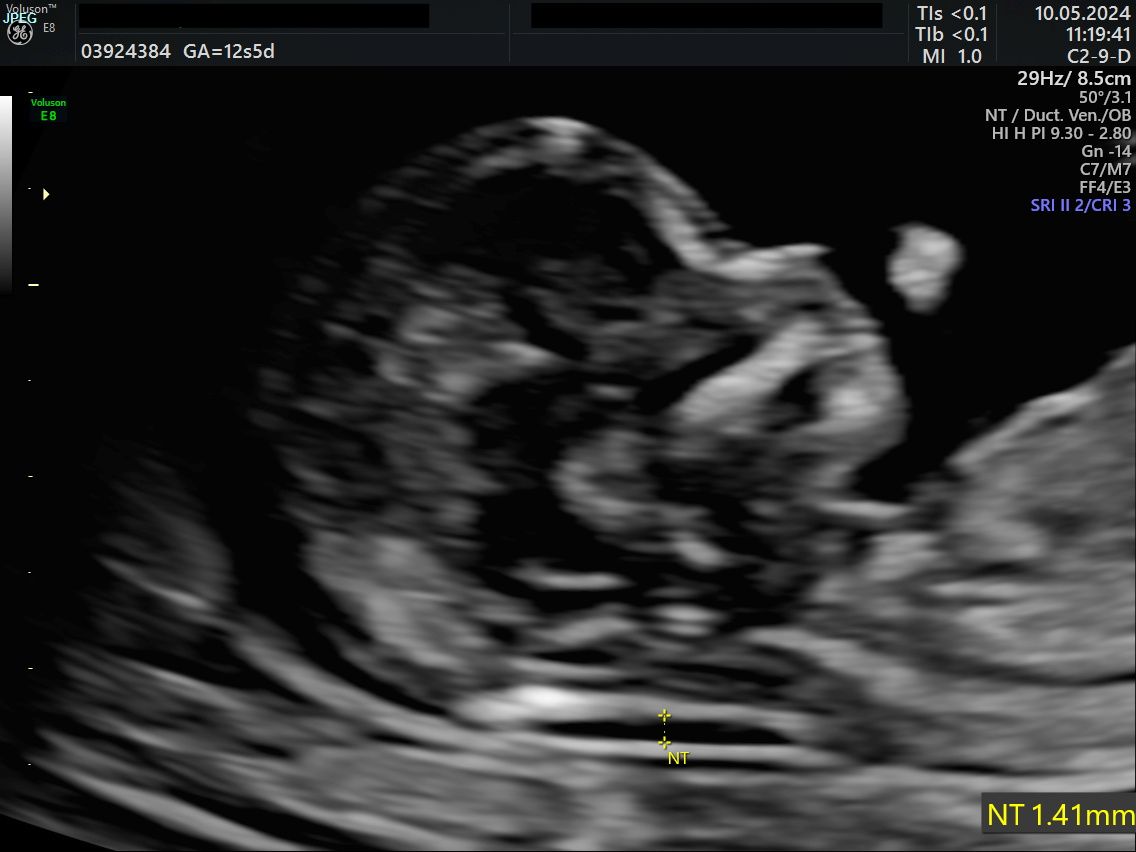

• Visite ed Ecografie Ostetriche: gestione della gravidanza fisiologica, translucenza nucale (membro accreditato ufficialmente), ecografia morfologica e del terzo trimestre